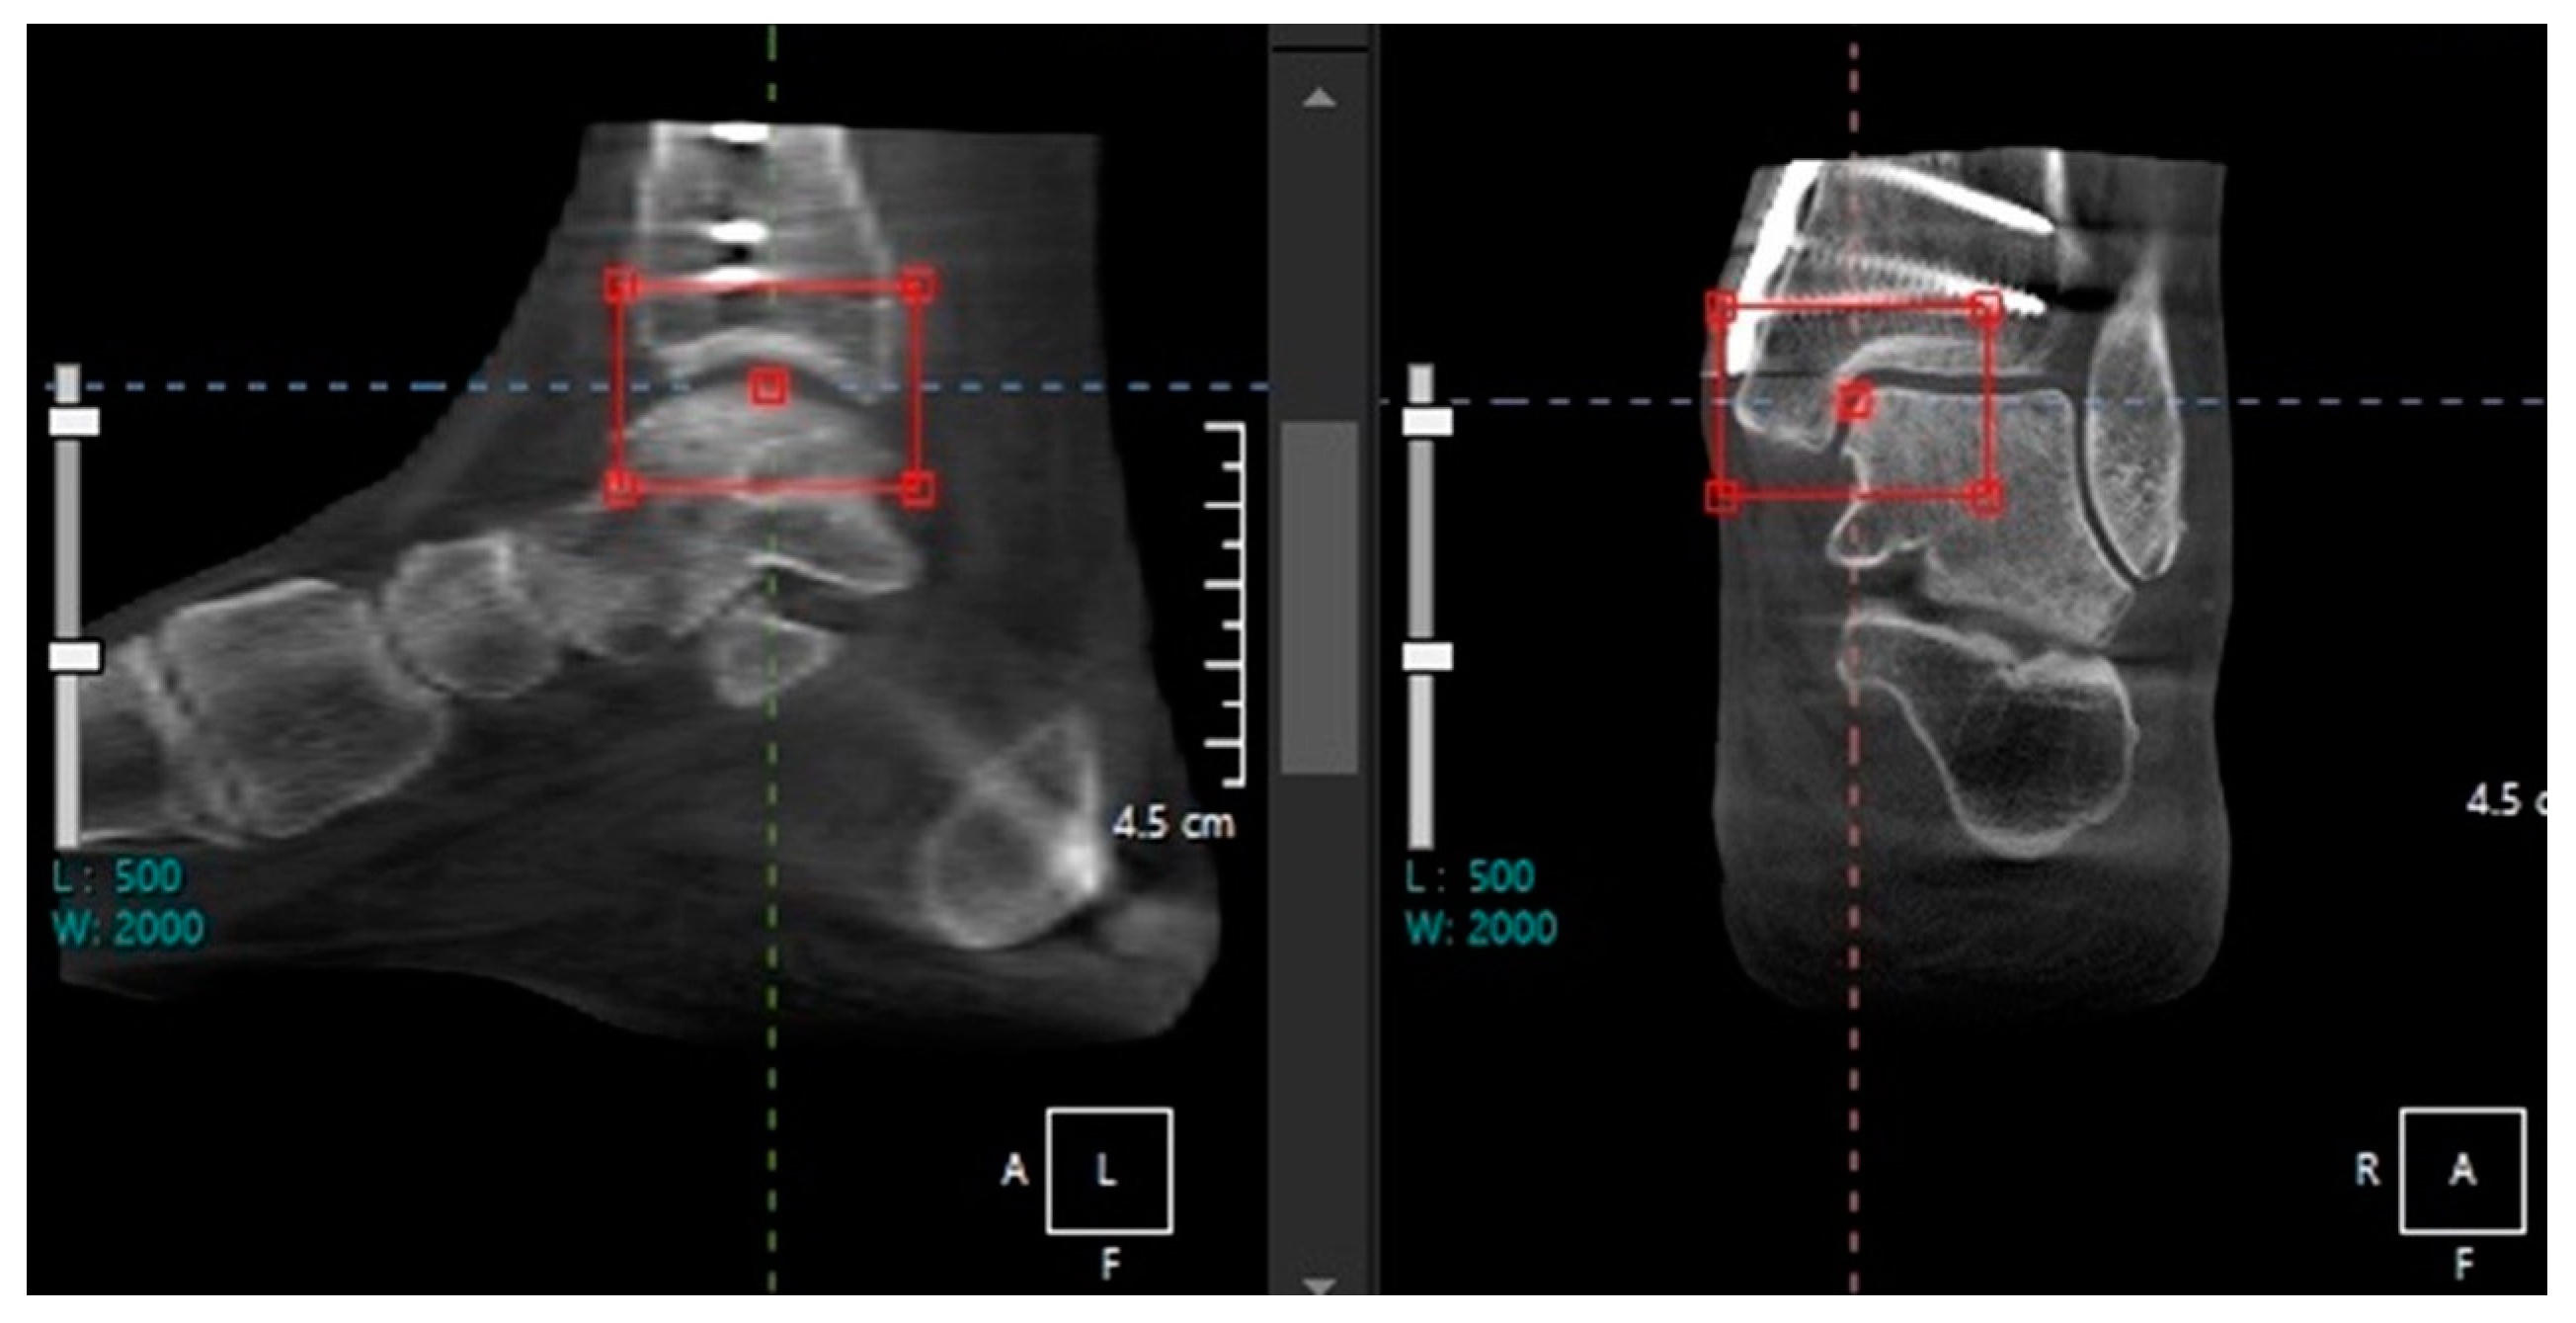

- Song, J.H.; Kang, C.; Kim, T.G.; Lee, G.S.; Lee, J.K.; Ahn, K.J.; Kim, D.H.; Lee, S.W. Perioperative axial loading computed tomography findings in varus ankle osteoarthritis: Effect of supramalleolar osteotomy on abnormal internal rotation of the talus. Foot Ankle Surg. 2021, 27, 217–223. [Google Scholar] [CrossRef]